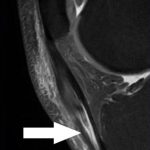

- NMR beeld ernstige ontsteking en partiële scheur middendeel achillespees bij 35j loper

Wanneer conservatieve therapie faalt is een NMR-evaluatie van de achillespees aangewezen om partiële rupturen uit te sluiten binnenin de pees, om de uitgebreidheid van de letsels te kunnen beoordelen, de lokalisatie en ook de peritendineuze structuren. Deze NMR zal de chirurg leiden in zijn operatie zodat hij ‘ziet’ waar het inflammatoir of littekenweefsel zich bevindt.